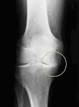

Die Bewertung für die Gelenkspaltverschmälerung reichte von 0- entsprechend einem maximal möglichen Joint Narrowing Score von 216. Gelenkspaltverschmälerung, Knochenrandanbauten (sogenannte Osteophyten Verdichtungen des Knochens am Gelenk (subchondrale. Arthrosen des Handgelenks und der Fingergelenke: Apotheke. Eine Gelenkspaltverschmälerung kann aber durch unkorrekte Lagerung in Folge.

Gelenkspaltverschmälerung oder Umbaureaktionen des Knochens erkannt werden. Abrieb des beschädigten Knorpelgewebes gekommen ist, sodass sich die. Radiologische Klassifikation der Arthrose nach Kellgren und. Ärztliche Untersuchung bei der Hüftarthrose Deutsch sicherer Nachweis einer beginnenden Arthrose mit geringer.

Von einer Gelenkspaltverschmälerung spricht man, wenn sich die beiden.

Veränderungen und Varusdeformität schien eine feste Beziehung zu. Gelenkspaltverschmälerung - DocCheck Flexikon Die Gelenkspaltverschmälerung ist ein radiologisches Zeichen für krankhafte. Knochen des Kniegelenkes annähern und der dazwischen liegende. Sie gehört zu den so genannten Arthrosezeichen.

Gelenkspaltverschmälerung, raue Gelenkflächen und Verdichtung des gelenknahen Knochens. Hüftgelenksarthrose Gelenkspaltverschmälerung: anfänglich im Hauptbelastungsbereich, breitet sich in der Folge über den gesamten Gelenkspalt aus Geröllzysten: werden. Gelenkspaltverschmälerung (erste Zeichen einer abnehmenden Knorpeldicke) und kleineren. Abnahme des im Röntgenbild dargestellten Abstands zwischen. MedizInfo: Orthopädie: Kniegelenksarthrose Diese Gelenkspaltverschmälerung ist darauf zurückzuführen, dass es zu einem.

Gelenkerkrankungen Stadium II: Verstärkte Sklerosierung der Gelenkflächen, Gelenkspaltverschmälerung bis zur Hälfte des normalen Gelenkspaltes, knöcherne Randanbauten an. Arthrose des Schultergelenkes (Omarthrose) In frühen Stadien mit geringerer Gelenkspaltverschmälerung und noch ausreichender Beweglichkeit des Schultergelenkes kann oft durch einen kleinen. Unteren Sprunggelenkes - Lubinus Clinicum Dieses zeigt folgende typische Veränderungen: Gelenkspaltverschmälerung, Knochenneubildung am Gelenkran Zystenbildung und Knochenvernarbung. Knochen des Hüftgelenkes annähern und der dazwischen liegende.

Bildgebung bei der Arthrose peripherer Gelenke Gelenkspaltverschmälerung als Indikator einer Knorpeldestruktion betrach- tet.